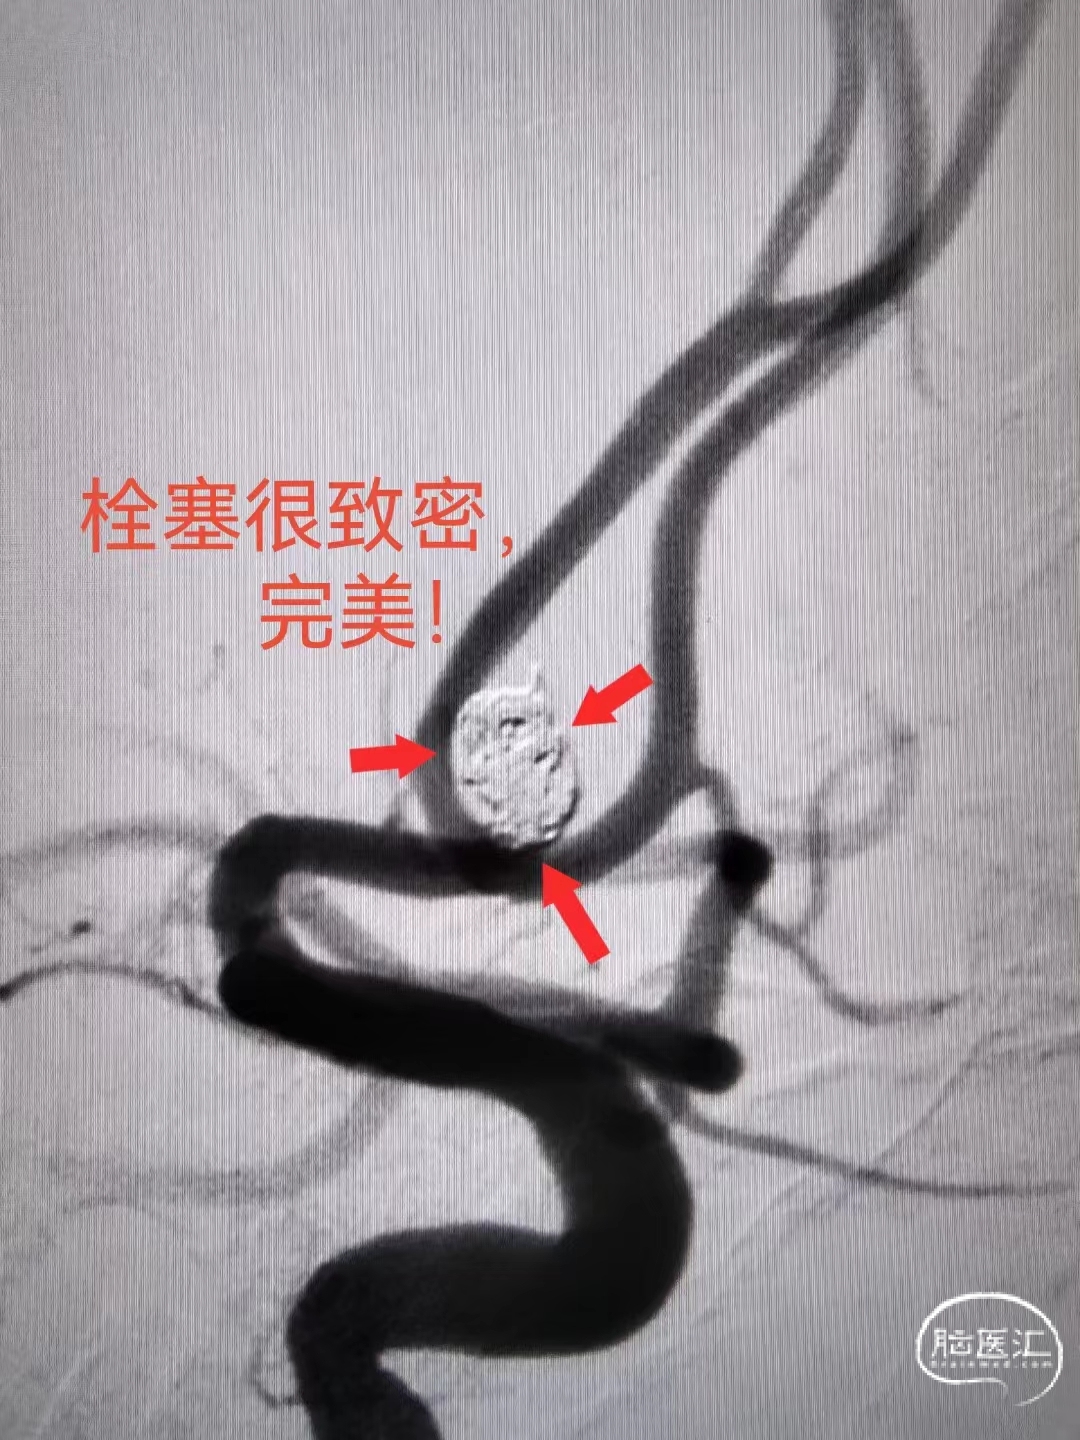

术后造影栓塞致密。

本次支架辅助下行动脉瘤栓塞,瘤颈处为特别重点,行致密填塞!

结果非常满意,影像学完美,应该为治愈级别栓塞了。